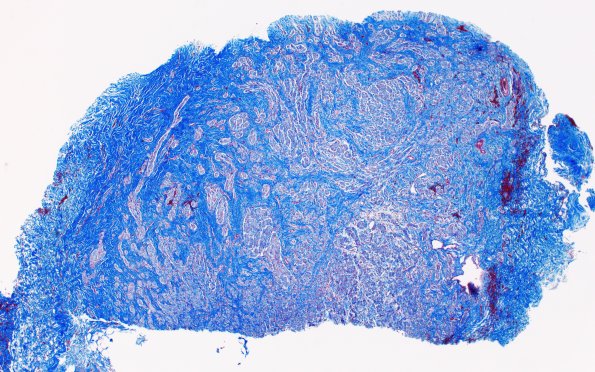

23G1 Neuroma (Case 23) Trichrome 4X

This trichrome stain shows prominent separation of mini-fascicles by bundles of collagen. (Trichrome)